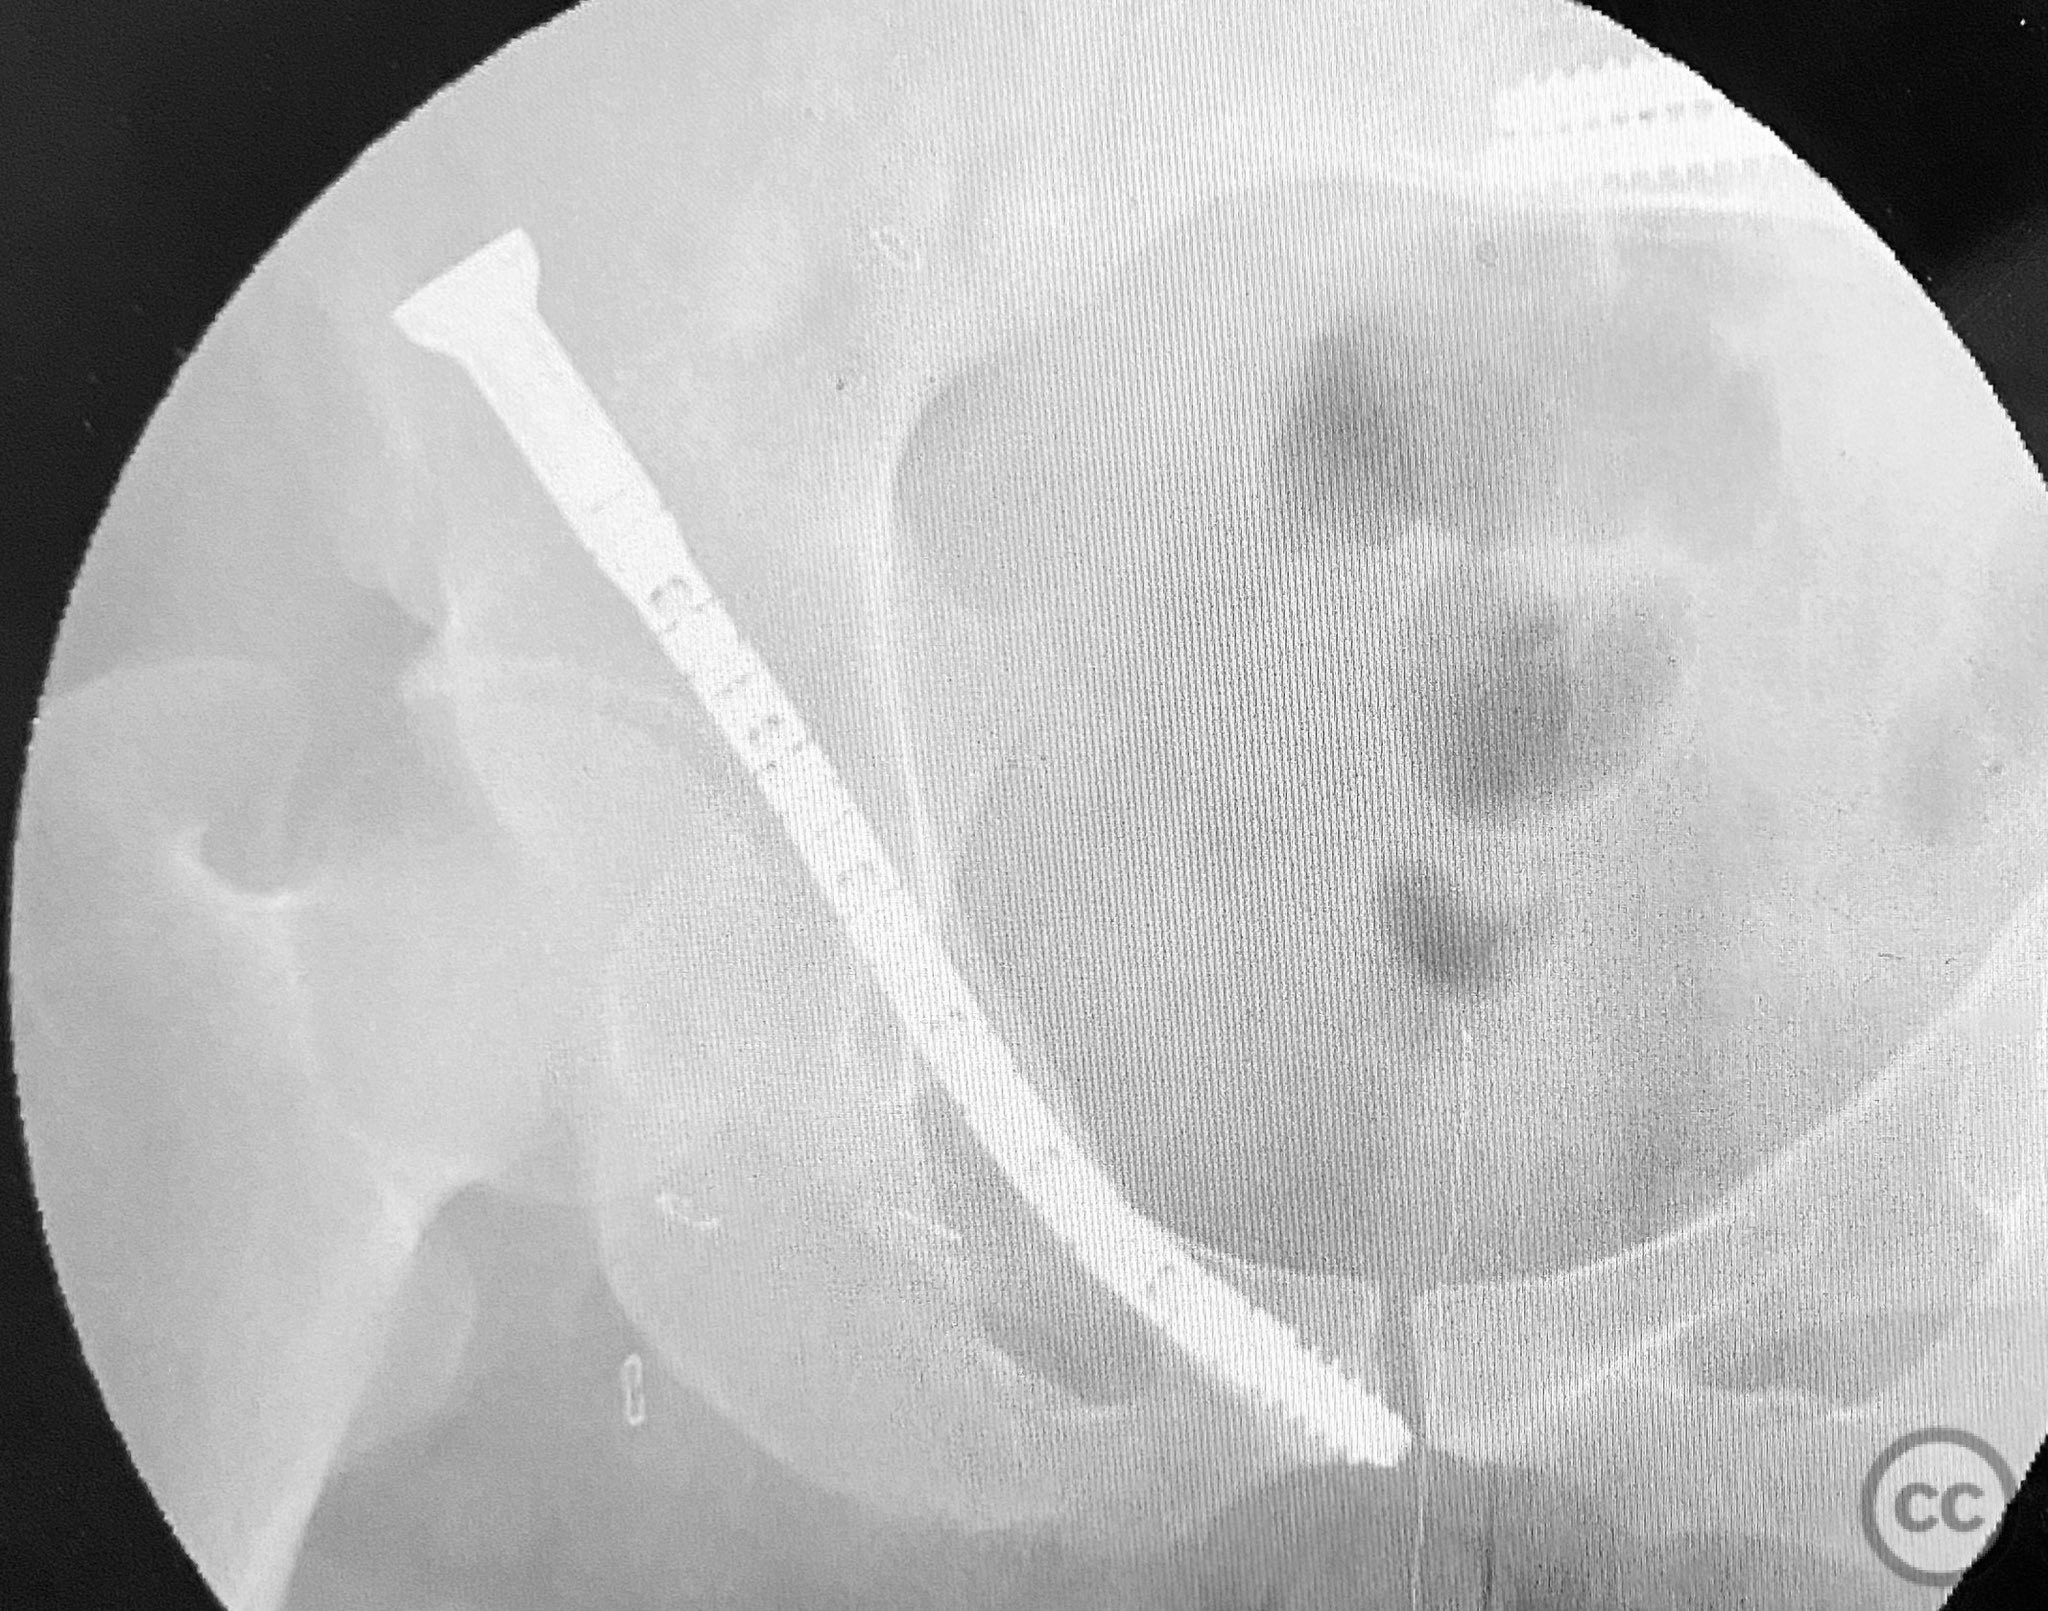

Pelvic Ring - AO/OTA 61x

Pelvis - AO/OTA 6x